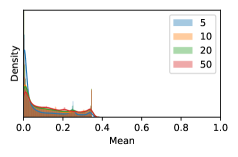

To model how different classifiers will respond to a given input , we assume that the prediction from classifier is sampled from a beta distribution that is characterized by two parameters by and . We further assume that is fixed to the same constant value for all ’s. Under this assumption, each input can be described by ( can be calculated since is fixed), easing further analysis. The Severity Level (SL) of the case represented by image can be characterized by the parameter . The larger the value of , the more severe the case of is. When and are close, the case is ambiguous as the distribution shifts towards being symmetric (i.e. signifying much disagreement among classifiers) rather than being one-sided (i.e. consensus among classifiers that is negative or positive). We provide a set of examples in Figure 2 and also Figure S.8 in the supplementary materials showing how the beta distribution can be used to capture diverse predictions given by an ensemble learner.

In contrast, the MC-dropout method showed the worst overall performance among the three, as it can be seen from the high ratios of SL0 examples among the uncertain negatives in Figure 4. The histograms in Figure 2 provides another perspective to look into the phenomenon, where a decent proportion of MC-dropout model’s predictions on SL0 inputs entailed low confidence (far from 0 or 1), which from another angle explained why MC-dropout was less specific in terms of lower FNP; many no-DR inputs (i.e. SL0) were erroneously assigned high uncertainty by MC-dropout models.

As discussed in Section 5.1 and Section 5.3 in the main paper, the mean metric and the stacking ensemble will have better performance in the precision (specificity) on the ambiguous data. Here, more detailed results are shown in Figures S.3 & S.6 and Table S.1. Figures S.3 & S.4 show the histograms of the uncertainty score for Kaggle-DR and Messidor-2 datasets that are the in-distribution (i.d.) dataset in our experiment and FigureS.5 & S.6 show the histograms for ImageNet and CIFAR-10 datasets, which is the o.o.d. datasets in our experiment. Each group of histograms contains results from the three evaluated ensemble methods (stacking ensemble, MC-dropout and TTA) and the three uncertainty metrics (mean, var and kl). Additional detailed results not displayed in Figure 4 can be found in Table S.1, which shows the proportion of the data of different SLs varies across different . For comparison, we also included in Table S.1 the results from single learners, and the proportions of data of different SLs (before any selection was made).